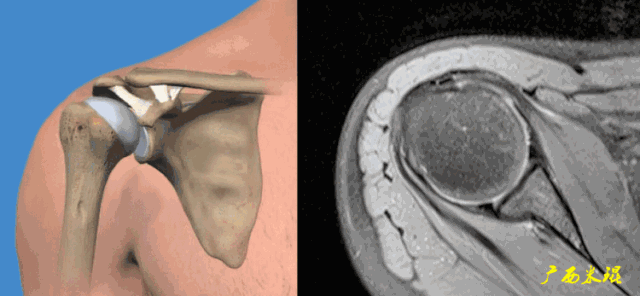

肩关节MRI检查扫描平面

(1)斜冠状位:平行于冈上肌腱长轴,主要评估冈上肌。

(2)斜矢状位:垂直于冈上肌长轴,观察肩峰形态及喙肩弓,观察肩袖4个组分的短轴断面。

(3)平行于关节盂/垂直于盂肱关节,主要评估盂唇,同时兼顾肩胛下肌、冈下肌及小圆肌。

正常肩袖的MRI表现

各个序列肩袖均表现为均匀的低信号,是肌腱的延续。